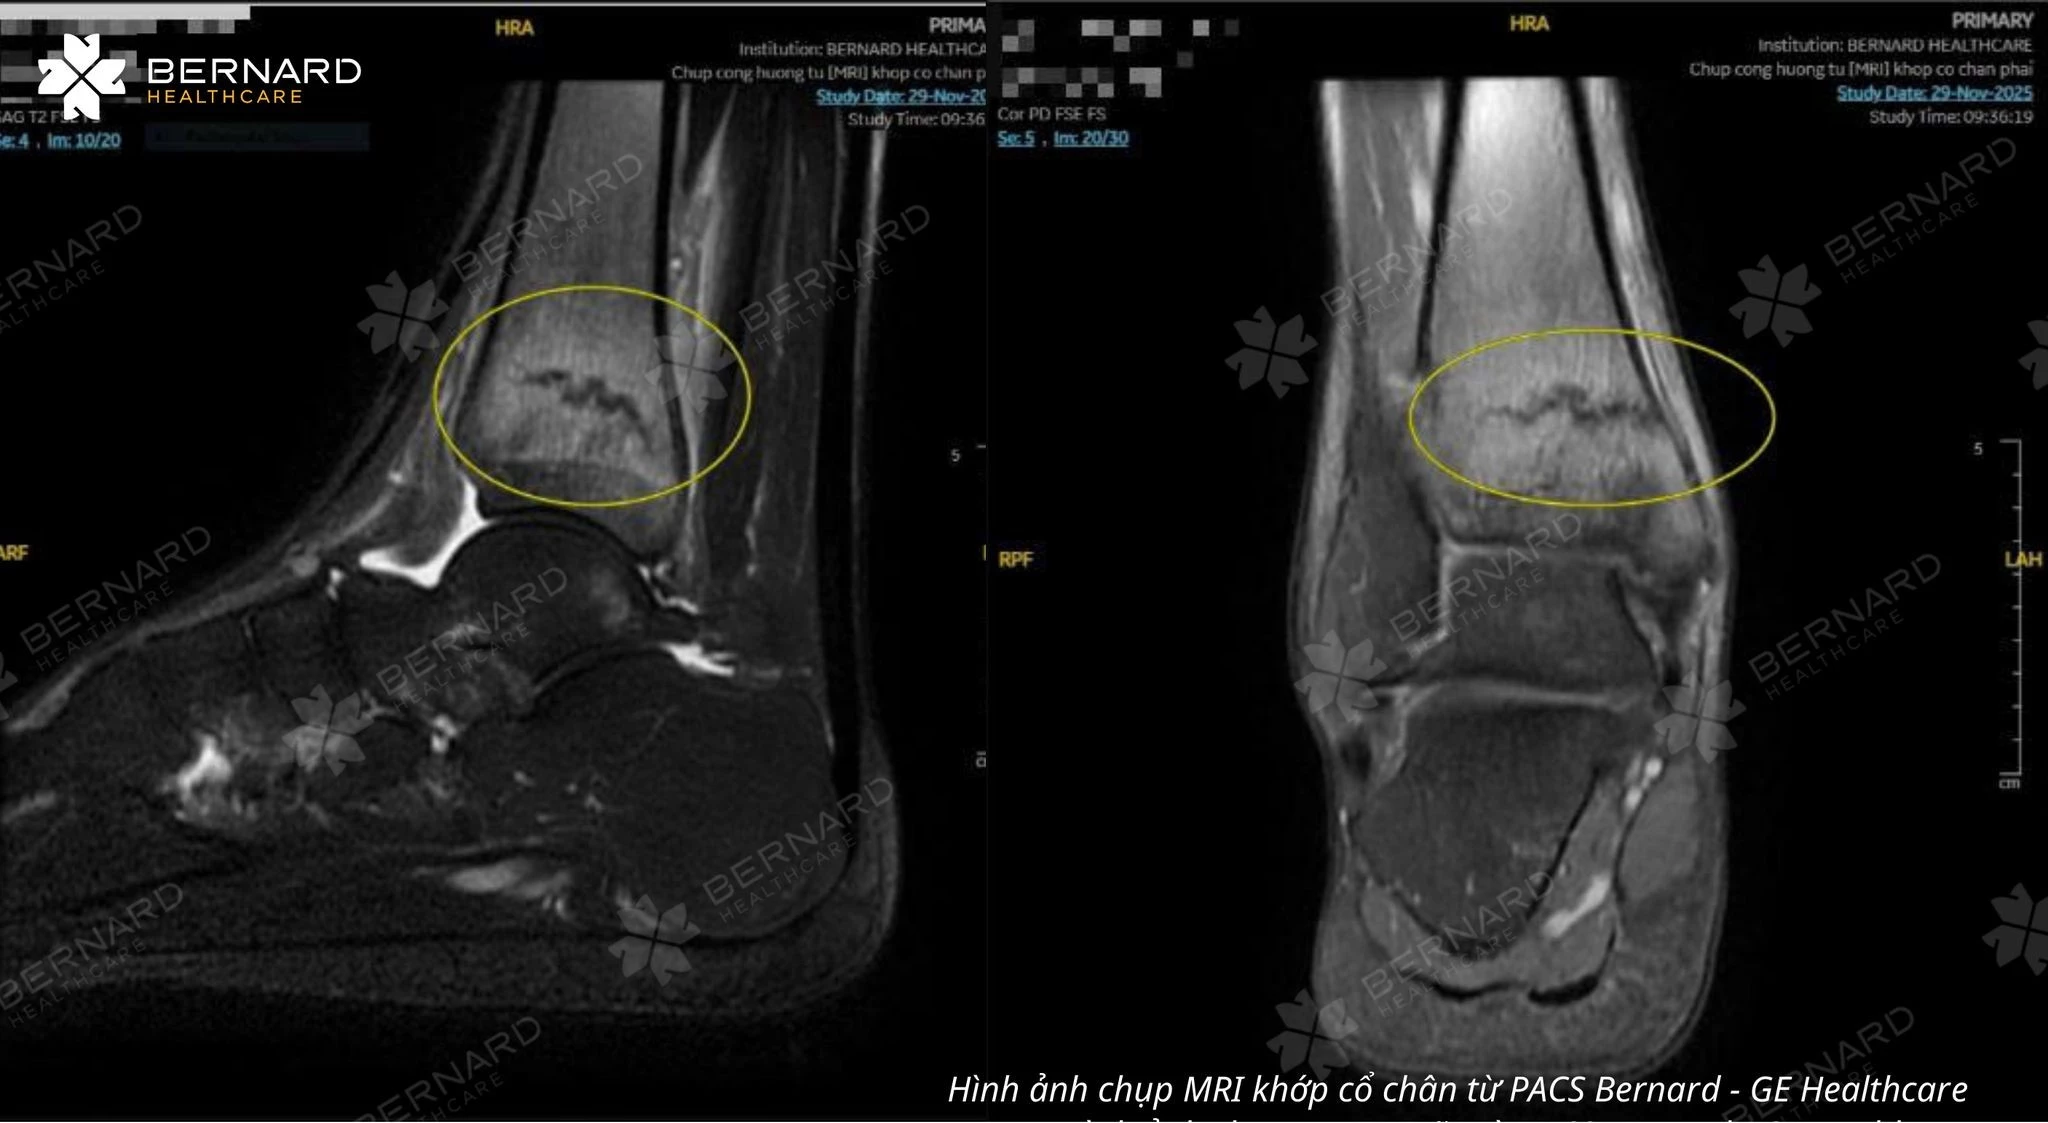

Trước biểu hiện trong không điển hình và nguy cơ bỏ sót tổn thương sâu trong khớp, bác sĩ chỉ định MRI khớp gối nhằm đánh giá toàn diện cấu trúc bên trong. Kết quả ghi nhận nhiều tổn thương phối hợp: tổn thương xương dưới sụn, thoái hóa sụn chêm, tổn thương sụn khớp kèm thay đổi mô mềm và nang Baker vùng khoeo.

Khác với các kỹ thuật chẩn đoán hình ảnh chỉ thể hiện tốt cấu trúc xương, MRI cho phép quan sát toàn diện cấu trúc khớp như một thể thống nhất, bao gồm xương, sụn, dây chằng, gân, bao khớp và các mô mềm xung quanh.

Nhờ khả năng tái tạo hình ảnh đa bình diện với độ tương phản mô cao, MRI giúp bác sĩ nhận diện những tổn thương rất sớm – ngay cả khi chưa gây biến đổi rõ rệt về hình thái hoặc chưa xuất hiện triệu chứng điển hình. Đây là ưu điểm then chốt giúp MRI vượt trội trong chẩn đoán các bệnh lý khớp phức tạp.